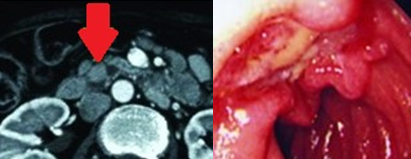

Liver after resection of the infected cyst. Presence of hemostatic Surgicel on the raw surface (Courtesy Dr. V. Penopoulos)

Polycystic liver disease. Red arrow. Infected hepatic cyst (Courtesy Dr. V. Penopoulos)